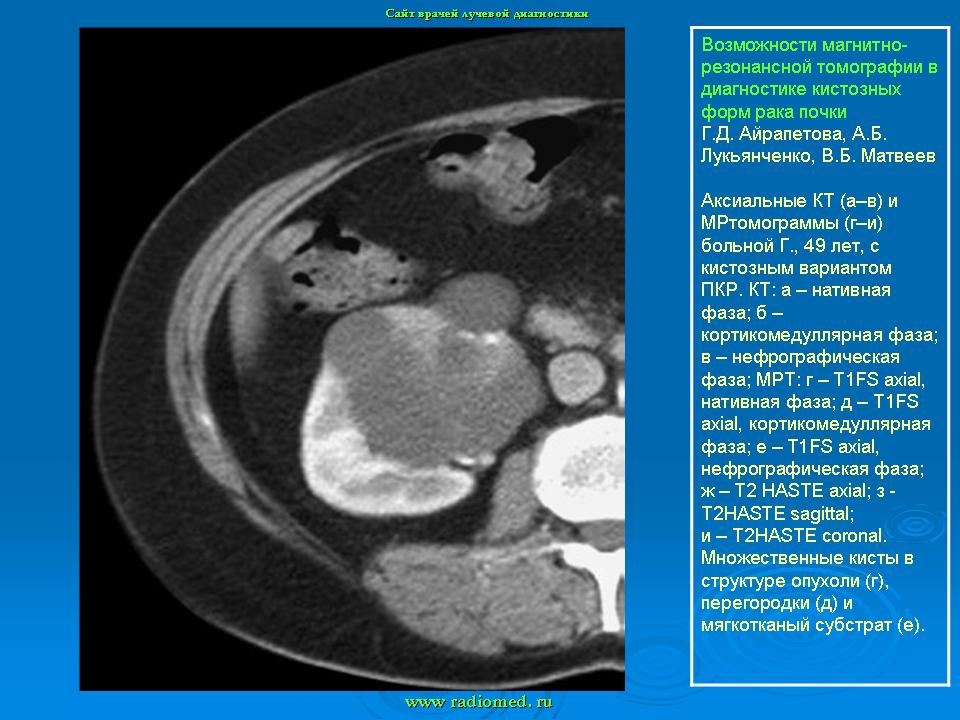

МРТ. Почки и мочевыводящие пути.